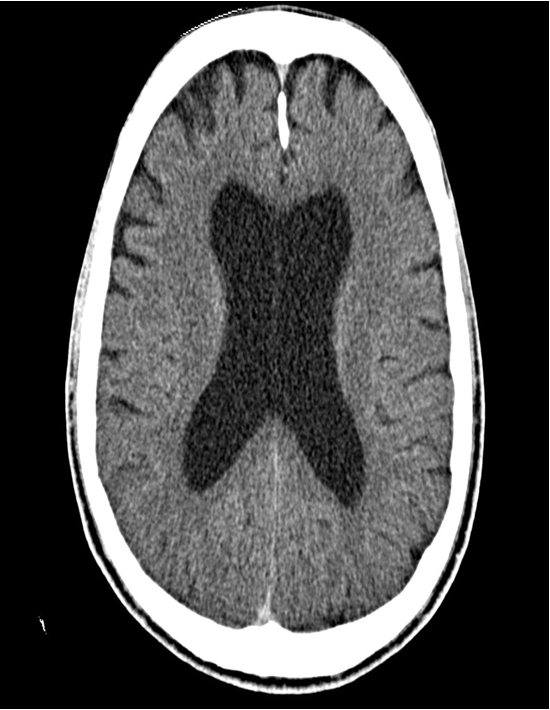

Cranial CT (axial view)

Significant enlargement of the lateral ventricles. The anterior falx cerebri appears hyperdense due to calcification.